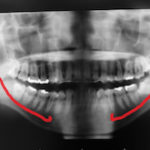

インプラント後のしびれ

こんにちは 理事長の亀井です。 インプラント治療は 現在多くの歯科医院で行われて ...